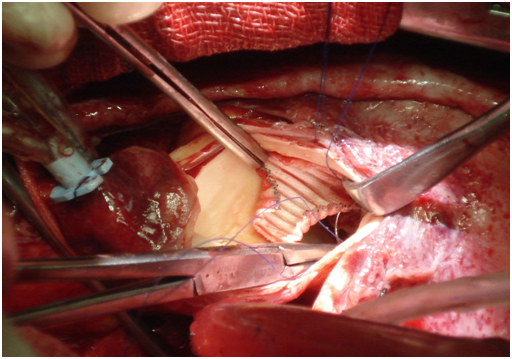

We presenting here a case of the patient with bicuspid aortic valve complicated with aneurysm of right sinus of valsalva. The aneurysm of sinus of valsalva was extracardiac and extending behind the main pulmonary artery and to the left. A 45years old Muslim male patient, carpenter by occupation was admitted with chief complaints of shortness of the breath and chest pain for 1 month. He was having orthopnoea and paroxysmal nocturnal dyspnoea and swelling of the feet. His vitals were stable with pulse rate 96/min, blood pressure 130/50mm Hg, and respiratory rate 14/min. On auscultation S1 was normal and S2 was soft with grade III/VI diastolic murmur in aortic area. Patient was properly investigated. ECG showed sinus rhythm and X-ray chest was showing cardiomegaly. Transthoracic echocardiography showed calcified bicuspid aortic valve, severe aortic regurgitation, grade II mitral regurgitation and that was appeared to be as dissecting flap in ascending aorta with 75% ejection fraction (Figure 1). Computed tomography chest was domne and it showed large pseudo-aneurysm of right sinus of Valsalva (Figures 2 & 3). Computed tomographic angiocardiography was done to define the lesion in the aorta accurately. Computed tomographic angiocardiography (Figures 4 & 5) revealed dysplastic aortic valve, para valvular aneurysmal sac communicating with aortic root as well as to left ventricle (? Pseudo-aneurysm). Routine investigations were done and patient was prepared for surgical intervention. Transoesophageal echocardiography was done in after induction of anaesthesia, which showed a large aneurysmal swelling behind the root of aorta. Conventional sternotomy was done. There were adhesions between pericardium and the heart. All adhesions were lysed. Aortotomy was done after institution of cardiopulmonary bypass. Bicuspid aortic valve and opening of the aneurysm were identified (Figure 6). Distorted, calcified aortic leaflets were excised and the opening of the aneurysm of sinus of valsalva was closed with Dacron patch from inside of the aorta (Figure 7). Aortic valve was replaced with sorin, bileaflet, mechanical valve, size 21 using interrupted ethibond, pladgeted sutures (Figure 8). Postoperative period was uneventful and patient was discharged on 7th postoperative day in good general condition. Patient is doing well in follow up visits.

Figure 7 Dacron patch closure of RSOV opening.

Figure 8 Aortic valve replacement with Mechanical valve.